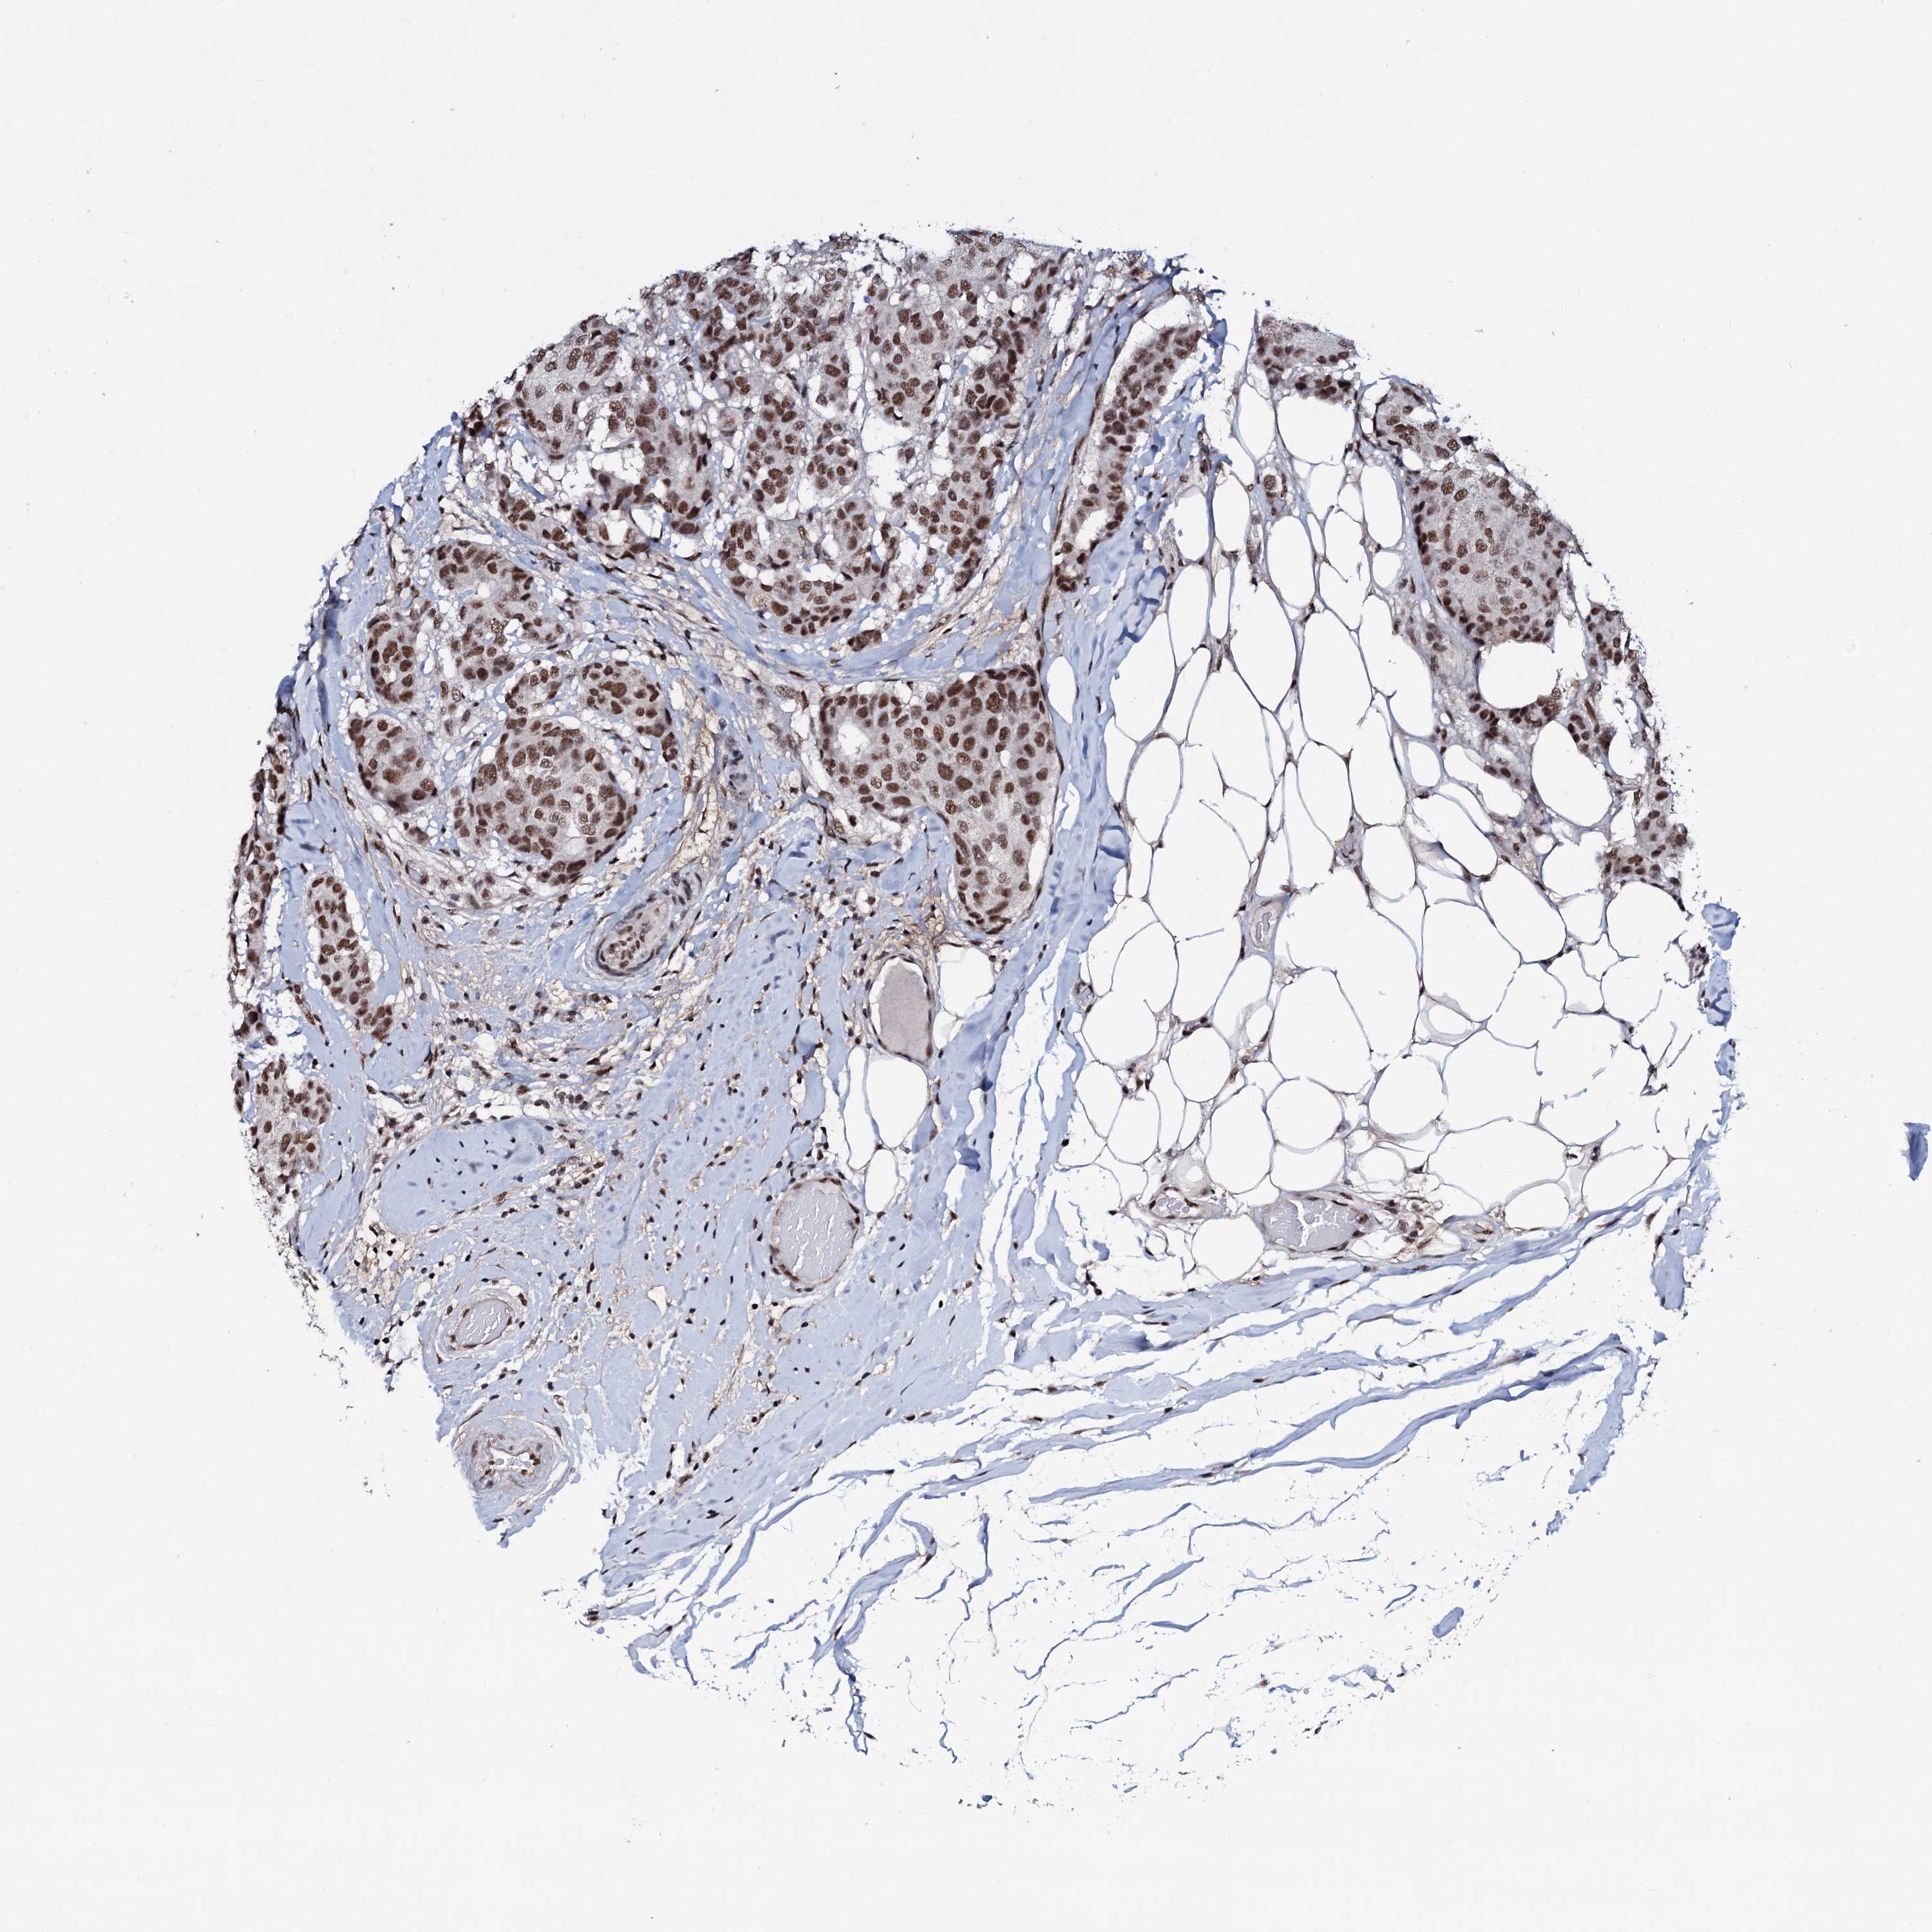

CANCER BREAST CANCER Show tissue menu

BRCA TCGA BRCA VALIDATION PROTEIN EXPRESSION

Breast cancer

Human cancer